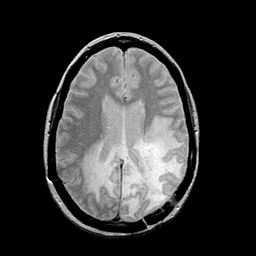

MR Study #2 -- Slice #33